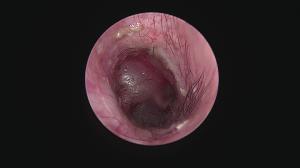

今回アップした動画は慢性外耳炎の中でも管理が困難な「耳垢腺過形成」による症例への治療動画になります

このような症例は管理が困難なため「全耳道切除」が一般的ですが、耳を摘出する手術は侵襲性が高いためなるべく避けたいところです。顔面神経麻痺などの副作用が懸念されます。

当院では内視鏡レーザー治療による緩和処置をすることで点耳薬による症状の改善を期待することができます

このような症例は案外多いため、一度精査を行い適切なケアをしてあげることがおすすめされます